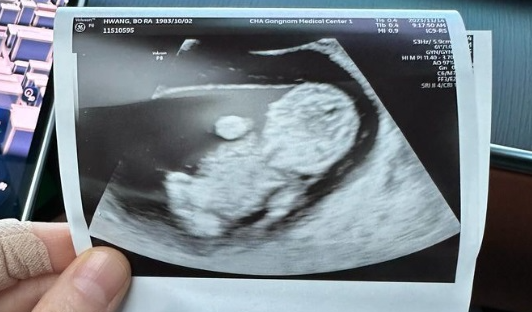

배우 황보라 씨가 출산 후 겪은 고통과 의료 파업과 관련된 오해에 대해 솔직하게 털어놨습니다. 그녀는 지난 5월 아들을 출산하며 제왕절개 수술을 받았고, 이 과정에서 겪은 고통과 이에 대한 자신의 발언으로 인해 많은 논란이 일었습니다. 이번 글에서는 황보라 씨의 출산 후 경험과 그에 따른 해명을 중심으로 자세히 알아보겠습니다.

황보라 씨는 "의료 파업 때문이라는 부적절한 표현을 사용한 것에 대해 신중하지 못한 점을 사과드린다"고 말하며, 담당 의료진과 병원 관계자들에게도 죄송한 마음을 전했습니다. 그녀는 앞으로 더 신중하게 발언할 것을 약속했습니다. 황보라 씨는 난임을 겪고 있던 중 시험관 시술을 4차례 시도한 끝에 임신에 성공했습니다.

그녀의 임신과 출산 소식은 많은 이들에게 큰 축하를 받았습니다. 황보라 씨는 "난임 극복부터 출산 과정, 그리고 새 생명의 탄생까지 축복해 주신 많은 분들께 감사의 말씀을 전합니다"라고 감사의 인사를 전했습니다. 한편, 보건복지부는 7월부터 제왕절개 등 분만 시 무통 주사와 페인버스터를 병용할 수 없다는 급여 기준 개정안을 행정예고 했습니다.